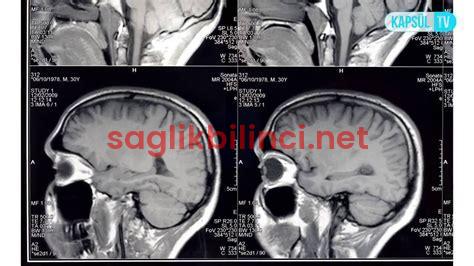

Araknoid Kist Nedir? Temel Bilgiler Araknoid kist, beyin ve omuriliği çevreleyen zarlar arasında oluşan, sıvı...